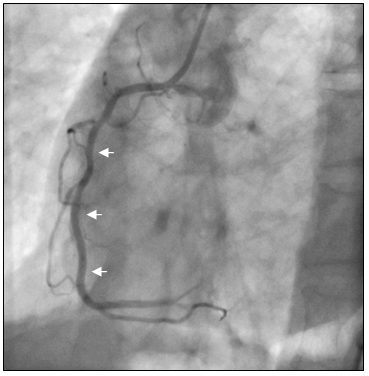

Tại cấp cứu bệnh nhân được chẩn đoán nhồi máu cơ tim cấp vùng hoành giờ thứ 2, block A-V độ 3, có chỉ định chụp mạch vành cấp cứu. Kết quả chụp mạch vành cho thấy hẹp nặng lan tỏa nhiều đoạn ở cả động mạch vành trái (hình 2a) và động mạch vành phải (hình 2b).

Hình 2b: Hệ mạch vành ưu thế phải, hẹp lan tỏa RCA